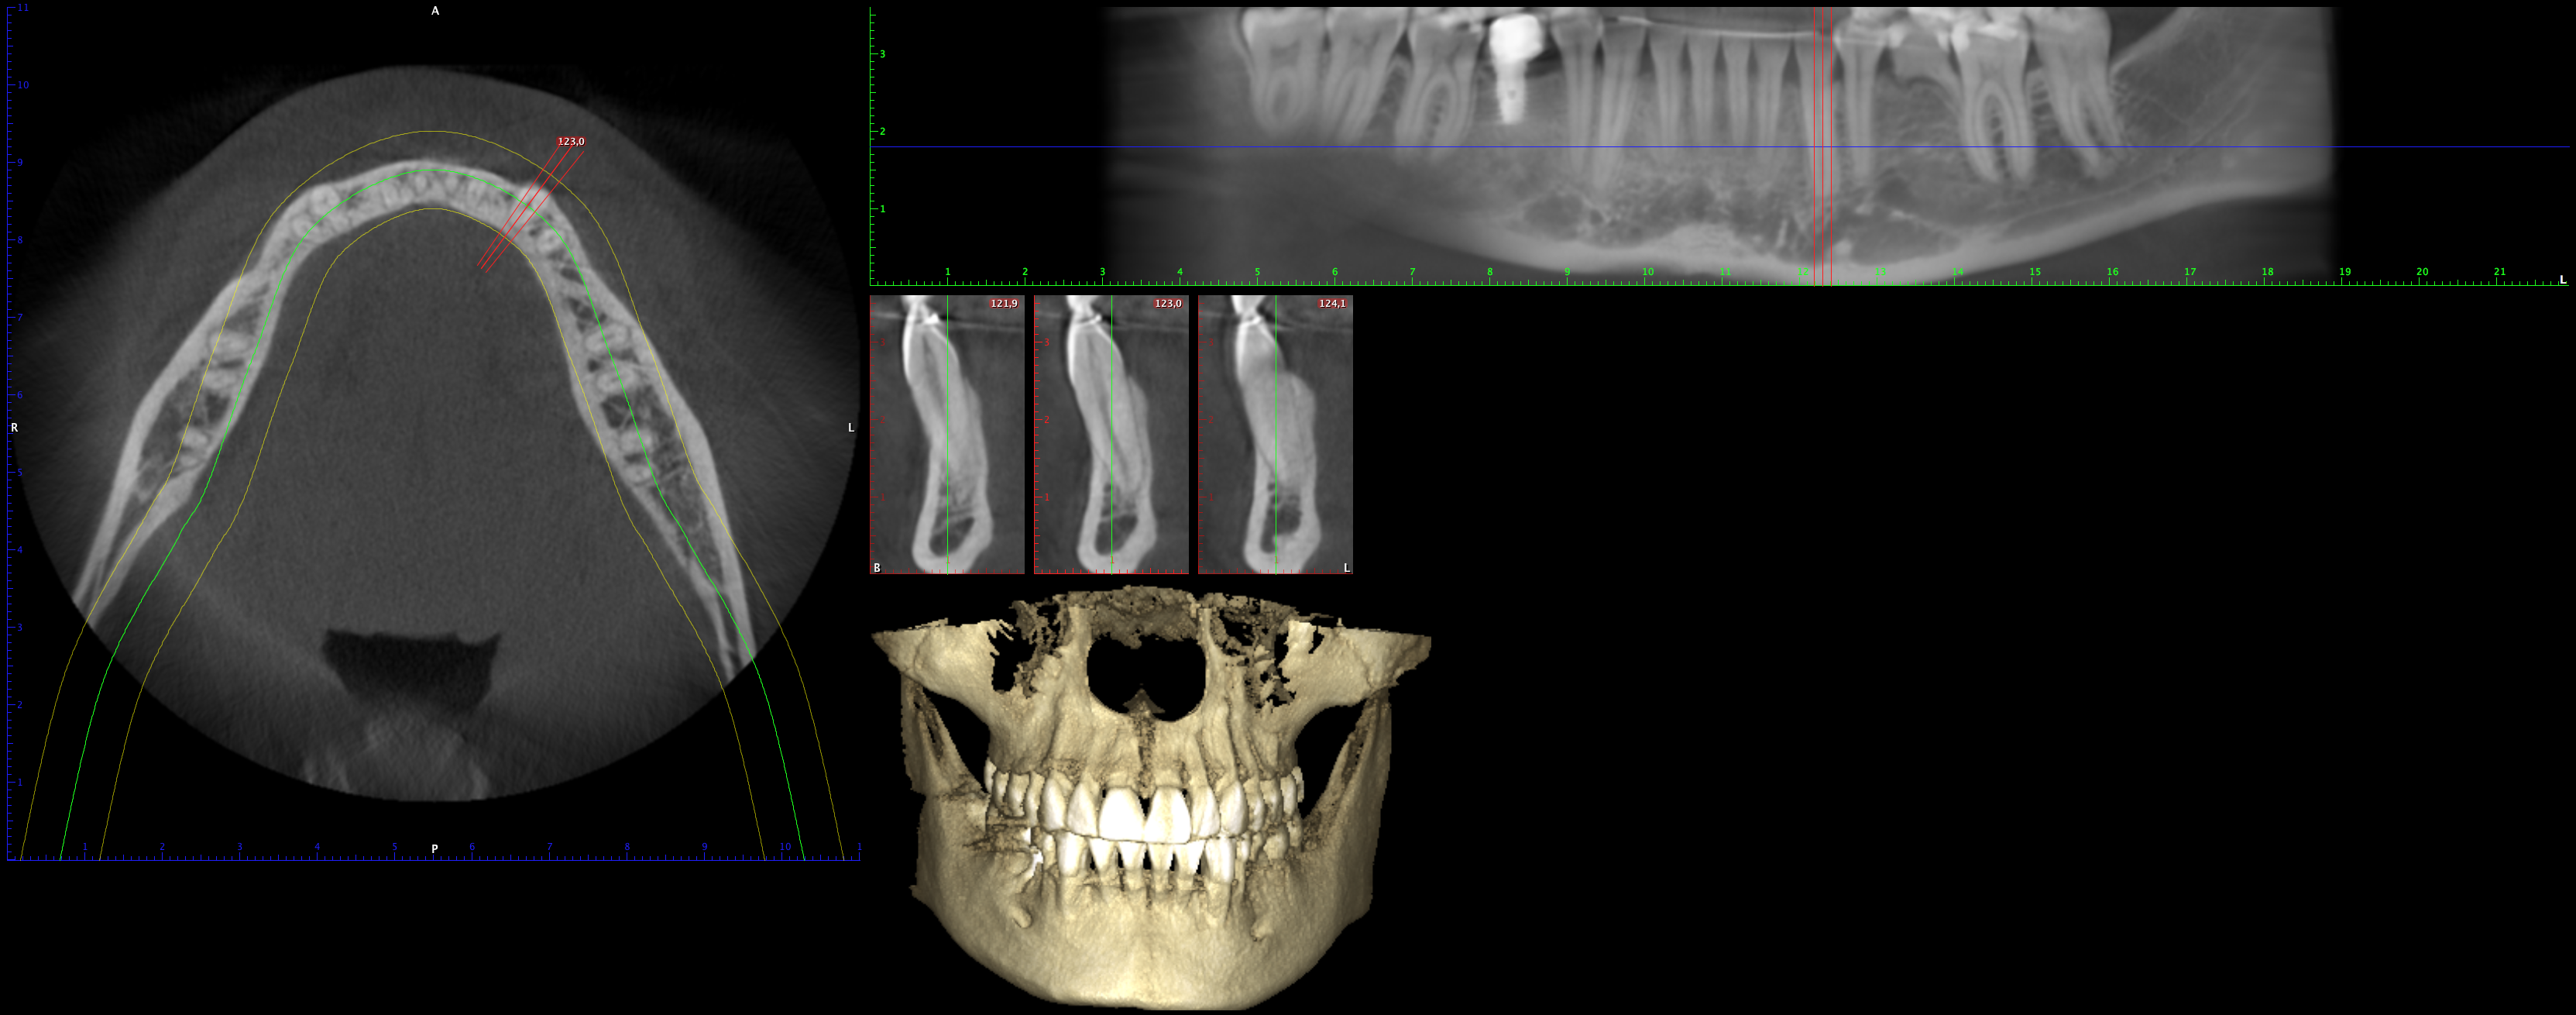

En PROTAC conseguimos una combinación ideal de calidad de imagen y usabilidad de alto nivel, ya que disponemos de una unidad CBCT(Cone Beam Computed Tomography) de última generación que supone un extraordinario avance en la evolución del procesamiento de imágenes de haz cónico, obteniendo una calidad de imagen optimizada, reduciendo los artefactos y garantizando imágenes de mayor contraste, para conseguir así satisfacer las necesidades del exigente procesamiento de imágenes maxilofaciales en todos los entornos clínicos. Nuestro innovador software Planmeca Romexis® ofrece herramientas especialmente diseñadas para especialistas en implantología, endodoncia, periodoncia, prostodoncia, ortodoncia, cirugía maxilofacial y otorrinolaringología.

Nuestra unidad de escáner y radiografía dental y nuestro software de procesamiento de imágenes brinda una combinación innovadora de imágenes 2D y 3D que le ofrecen una visión más completa para conocer con mayor exactitud las necesidades de sus pacientes.

Unidad CBCT de última generación con una calidad de imagen optimizada.

Software con herramientas especializadas para implantología, endodoncia, periodoncia, prostodoncia, ortodoncia, cirugía maxilofacial y otorrinolaringología.

Imágenes 2D y 3D más completas para conocer con mayor exactitud las necesidades de sus pacientes.